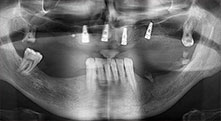

Piezomed B6

Der Kieferkamm wird beidseitig piezochirurgisch gespalten (Instrument: Piezomed B6). Die Implantation erfolgt im selben Eingriff und der periimplantäre Knochen wird zusätzlich mit einer GBR-Maßnahme aufgebaut.

Implantate

Die vier Implantate befinden sich wie geplant in situ. Die distalen Oberkiefermolaren dienen noch zur Fixierung der unterfütterten Prothese, die einen Monat nach Implantation eingegliedert wird.